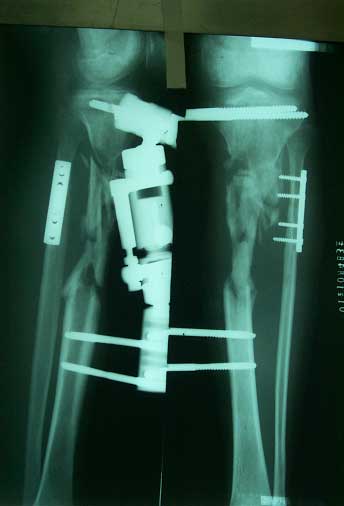

异体皮质骨桥接骨缺损,将混合红骨髓的异体松质骨填充缺损区

术前X线片,骨折后2年骨缺损、骨不连     术后6个月X线片,新骨桥接骨缺损